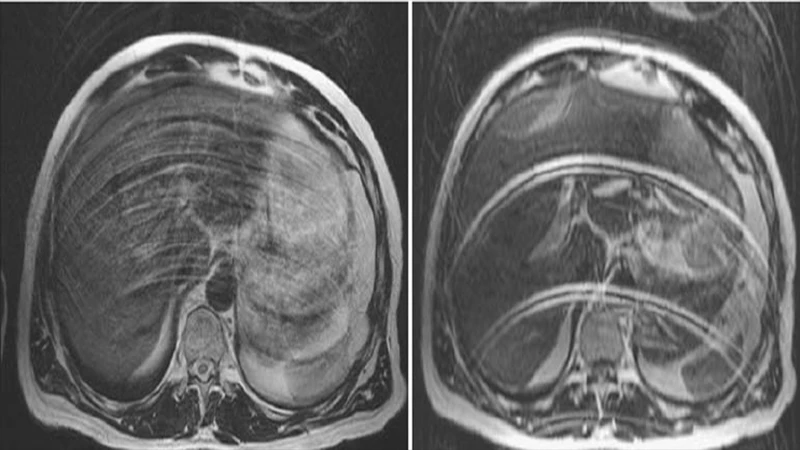

1. Motion Artifact

This is the most common artifact across all imaging modalities. It occurs when the patient moves during the scan acquisition, resulting in blurring, ghosting, or streaking across the image.

• Appearance: Blurry or smeared anatomy, ghost-like repetitions of structures.

• Cause: Voluntary (e.g., patient moving a limb) or involuntary (e.g., breathing, heartbeat, peristalsis) patient movement.

• Solution:

• Clear Communication: Carefully explain the importance of holding still to the patient. Use clear breath-hold instructions.

• Immobilization: Use straps, pads, and cushions to help the patient remain comfortable and still.

• Technique: Use faster imaging sequences when possible. For MRI, techniques like respiratory gating can synchronize the scan with the patient's breathing.

An axial MRI of the brain showing severe motion artifact, with ghosting and blurring across the image.